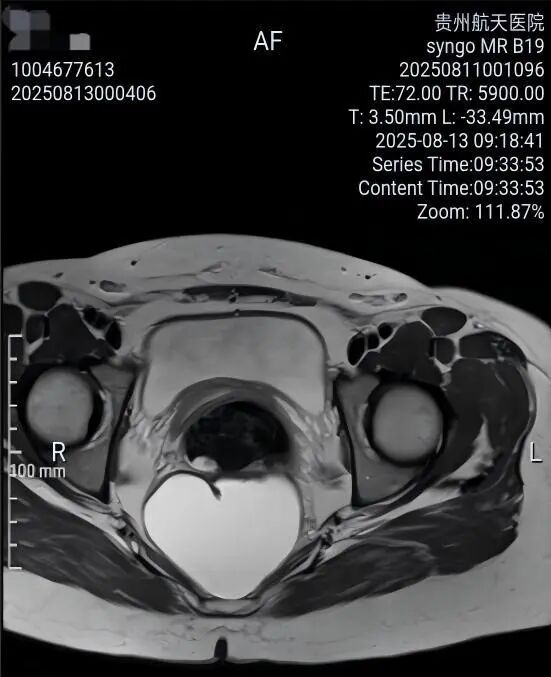

一名女性患者长期受到下腹部坠胀、排便不适等症状困扰,近期发现盆腔内存在肿物,严重影响其生活质量,为寻求进一步诊治,她前往贵州航天医院普外科就诊,经核磁共振(MRI)检查提示:盆腔内直肠与骶骨之间有一个“骶前囊肿”。由于该囊肿位置深,且与周围重要的神经和血管关系密切,若采用传统手术不仅创伤大,还伴随一定的风险。 面对这一棘手难题,普外科立即组织了麻醉科、医学影像科、妇科、重症医学科在内的多学科专家会诊(MDT)。经专家团队详细评估,与患者及家属充分沟通后,为患者制定并成功实施了“腹腔镜下骶前囊肿切除术”。术后恢复良好,不久便康复出院。 【疾病科普|什么是骶前囊肿?】 骶前囊肿,可以理解为生长在骨盆最深处、直肠后方的一个囊性肿物。由于它“躲藏”的位置非常特殊,四周紧邻着控制排便和感觉的重要神经与血管,因此被视为盆腔外科手术中的一个难点。 它可能带来哪些影响? 1.随着囊肿逐渐增大,可能会压迫直肠,引起排便困难或坠胀感。 2.压迫骶神经,可能导致腰骶部或会阴区的酸胀、疼痛。 3.囊肿本身也可能发生感染,形成脓肿,加重不适。 【技术介绍|腹腔镜下骶前囊肿切除术】 对于骶前囊肿这类较深的病灶,腹腔镜下骶前囊肿切除术提供了一种更为微创、便于操作的解决方案。 它是如何进行的? 医生仅通过腹部几个约0.5-1厘米的小孔,其中一个孔放入带高清摄像头的腹腔镜,将盆腔内的景象放大并清晰地投射到屏幕上,如同给了医生一双进入体内的“眼睛”。其他几个小孔则伸入细长的专用手术器械。医生看着屏幕,遥控这些器械,在清晰的视野下精细地分离并完整切除囊肿。 腹腔镜微创手术的特点包括: ▶创伤较小:避免了传统手术的长切口,体表疤痕小。 ▶视野清晰:放大后的图像让医生能更清楚地分辨囊肿与周围重要结构。 ▶操作精准:有助于更完整地切除囊肿,并尽力保护盆腔神经功能。 ▶恢复较快:因手术创伤小,患者术后疼痛感更轻,下床活动早,住院时间也可能缩短。 注:本文旨在进行健康科普,分享医疗案例与科普知识,不能替代任何专业的医疗建议。如有任何健康问题,请务必及时咨询并遵从专业医生的诊疗意见。 贵州航天医院普外科专家简介 高大勇 普外科(肛肠外科)学科带头人、名誉主任,主任医师、教授 临床擅长:对中西医结合诊治肛肠学科各种常见病、多发病及疑难杂症等具有丰富的临床经验。 原遵义市第一人民医院(遵义医科大学第三附属医院)、遵义市中医院肛肠科主任。中华中医药学会肛肠分会常委,全国中医肛肠学科名专家,中国健康促进与教育协会肛肠分会常委,中国康复医学会肛肠疾病康复专业委员会常委,中国民间中医医药研究开发协会肛肠分会副秘书长,中国医师协会中西医结合肛肠医师专业委员会常委,国家二级心理咨询师,贵州省第一批中医名医工作指导老师,遵义市名中医,遵义市肛肠学会会长,遵义市肛肠质控中心名誉主任,遵义市中西医结合学会名誉会长,遵义市健康科普专家,原贵州省中西医结合学会肛肠分会副主任委员、贵州省中医肛肠质控中心副主任、遵义市医学会医疗鉴定委员会专家、遵义市卫生系列高级评委。发表论文30余篇,主编和参编医学著作5本,主持省级科研课题2项、市级科研课题2项、院级科研课题1项。 梁 跃 普外科党支部书记、主任,主任医师 临床擅长:对普外科各类肿瘤手术具有丰富的临床经验。 毕业于遵义医学院,遵义市医学会小儿外科学分会常务委员,遵义市肛肠协会理事,遵义市医学会核医学分会(第二届)委员会委员;荣获第三期“黔医人才计划”优秀学员称号;主持市级课题1项,完成省级课题1项,在国内各类刊物上发表论文10余篇。 钱科洪 民盟盟员,普外科副主任医师 临床擅长:从事普外科临床工作30余年,对各类普外科疾病的诊治、乳腺、甲状腺、胃十二指肠、结直肠等疾病及疑难杂症具有丰富的临床经验。 毕业于遵义医学院临床医疗系,2009年前往中山大学附属第一医院微创外科进修学习,在国内各专业期刊发表论文数篇。 贵州航天医院普外科简介 基本情况 贵州航天医院普外科成立于1968年,前身属于原航天部O61基地3417医院外一科,1998年3417医院、3427医院合并后更名为普外科,下设胃肠外科、肛肠外科2个亚专业科室,拥有在全市较为先进的专科设备和技术,是中国疝病专科联盟单位,贵州医科大学附属医院胃肠外科专科联盟单位。开放床位40张,配备医护人员21人。 专科特色 普外科致力于胃肠及肛肠疾病的外科临床诊治及科研,以腹腔镜微创外科技术为本,形成以快速康复治疗胃肿瘤、结直肠肿瘤、小肠肿瘤、直肠脱垂、肥胖病、急腹症、各类疝、痔、瘘等专科特色,同时注重胃肠疾病尤其是结直肠恶性肿瘤的基础研究和临床转化研究,总体诊断和治疗水平在区域同级医院居于领先水平。 开展手术:腹腔镜下胃癌根治术,腹腔镜下袖状胃切除术,腹腔镜下胃肠道间质瘤切除术,腹腔镜下结、直肠癌根治术,胃癌、结直肠癌的精准治疗,腹腔镜下小儿疝气、成人疝修补术,腹腔镜下阑尾手术,内痔的硬化注射治疗及痔疮的微创治疗:ATH、PPH、TST,直肠脱垂的各种手术治疗,难治性伤口VSD技术,鼻胃肠管、肠梗阻导管置入术,肛肠术后间歇性导尿技术,并引进了中医适宜技术,也为各种化疗患者提供输液港安装,提高患者就医体验。 腹腔镜下腹股沟疝 无张力修补术 腹股沟疝里金斯坦 (Lichtenstein)手术 PPH微创术治疗环状混合痔 黏连性或炎性肠梗阻-肠梗阻导管 腹腔镜袖状胃切除 腹腔镜阑尾切除术 腹腔镜阑尾肿瘤切除术 腹腔镜下结肠癌根治术 诊疗范围 胃肿瘤、结直肠肿瘤、小肠肿瘤、肥胖症、各类急腹症、腹部外伤、腹壁疝、便秘、直肠脱垂、痔疮、肛瘘、肛裂等胃肠、肛肠外科疾病。 END